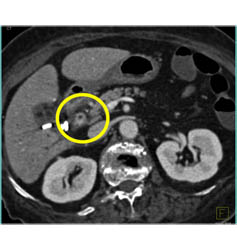

Cholangiocarcinoma of the Distal Common Bile Duct (CBD) Which Is Enhancing- See Full Sequence